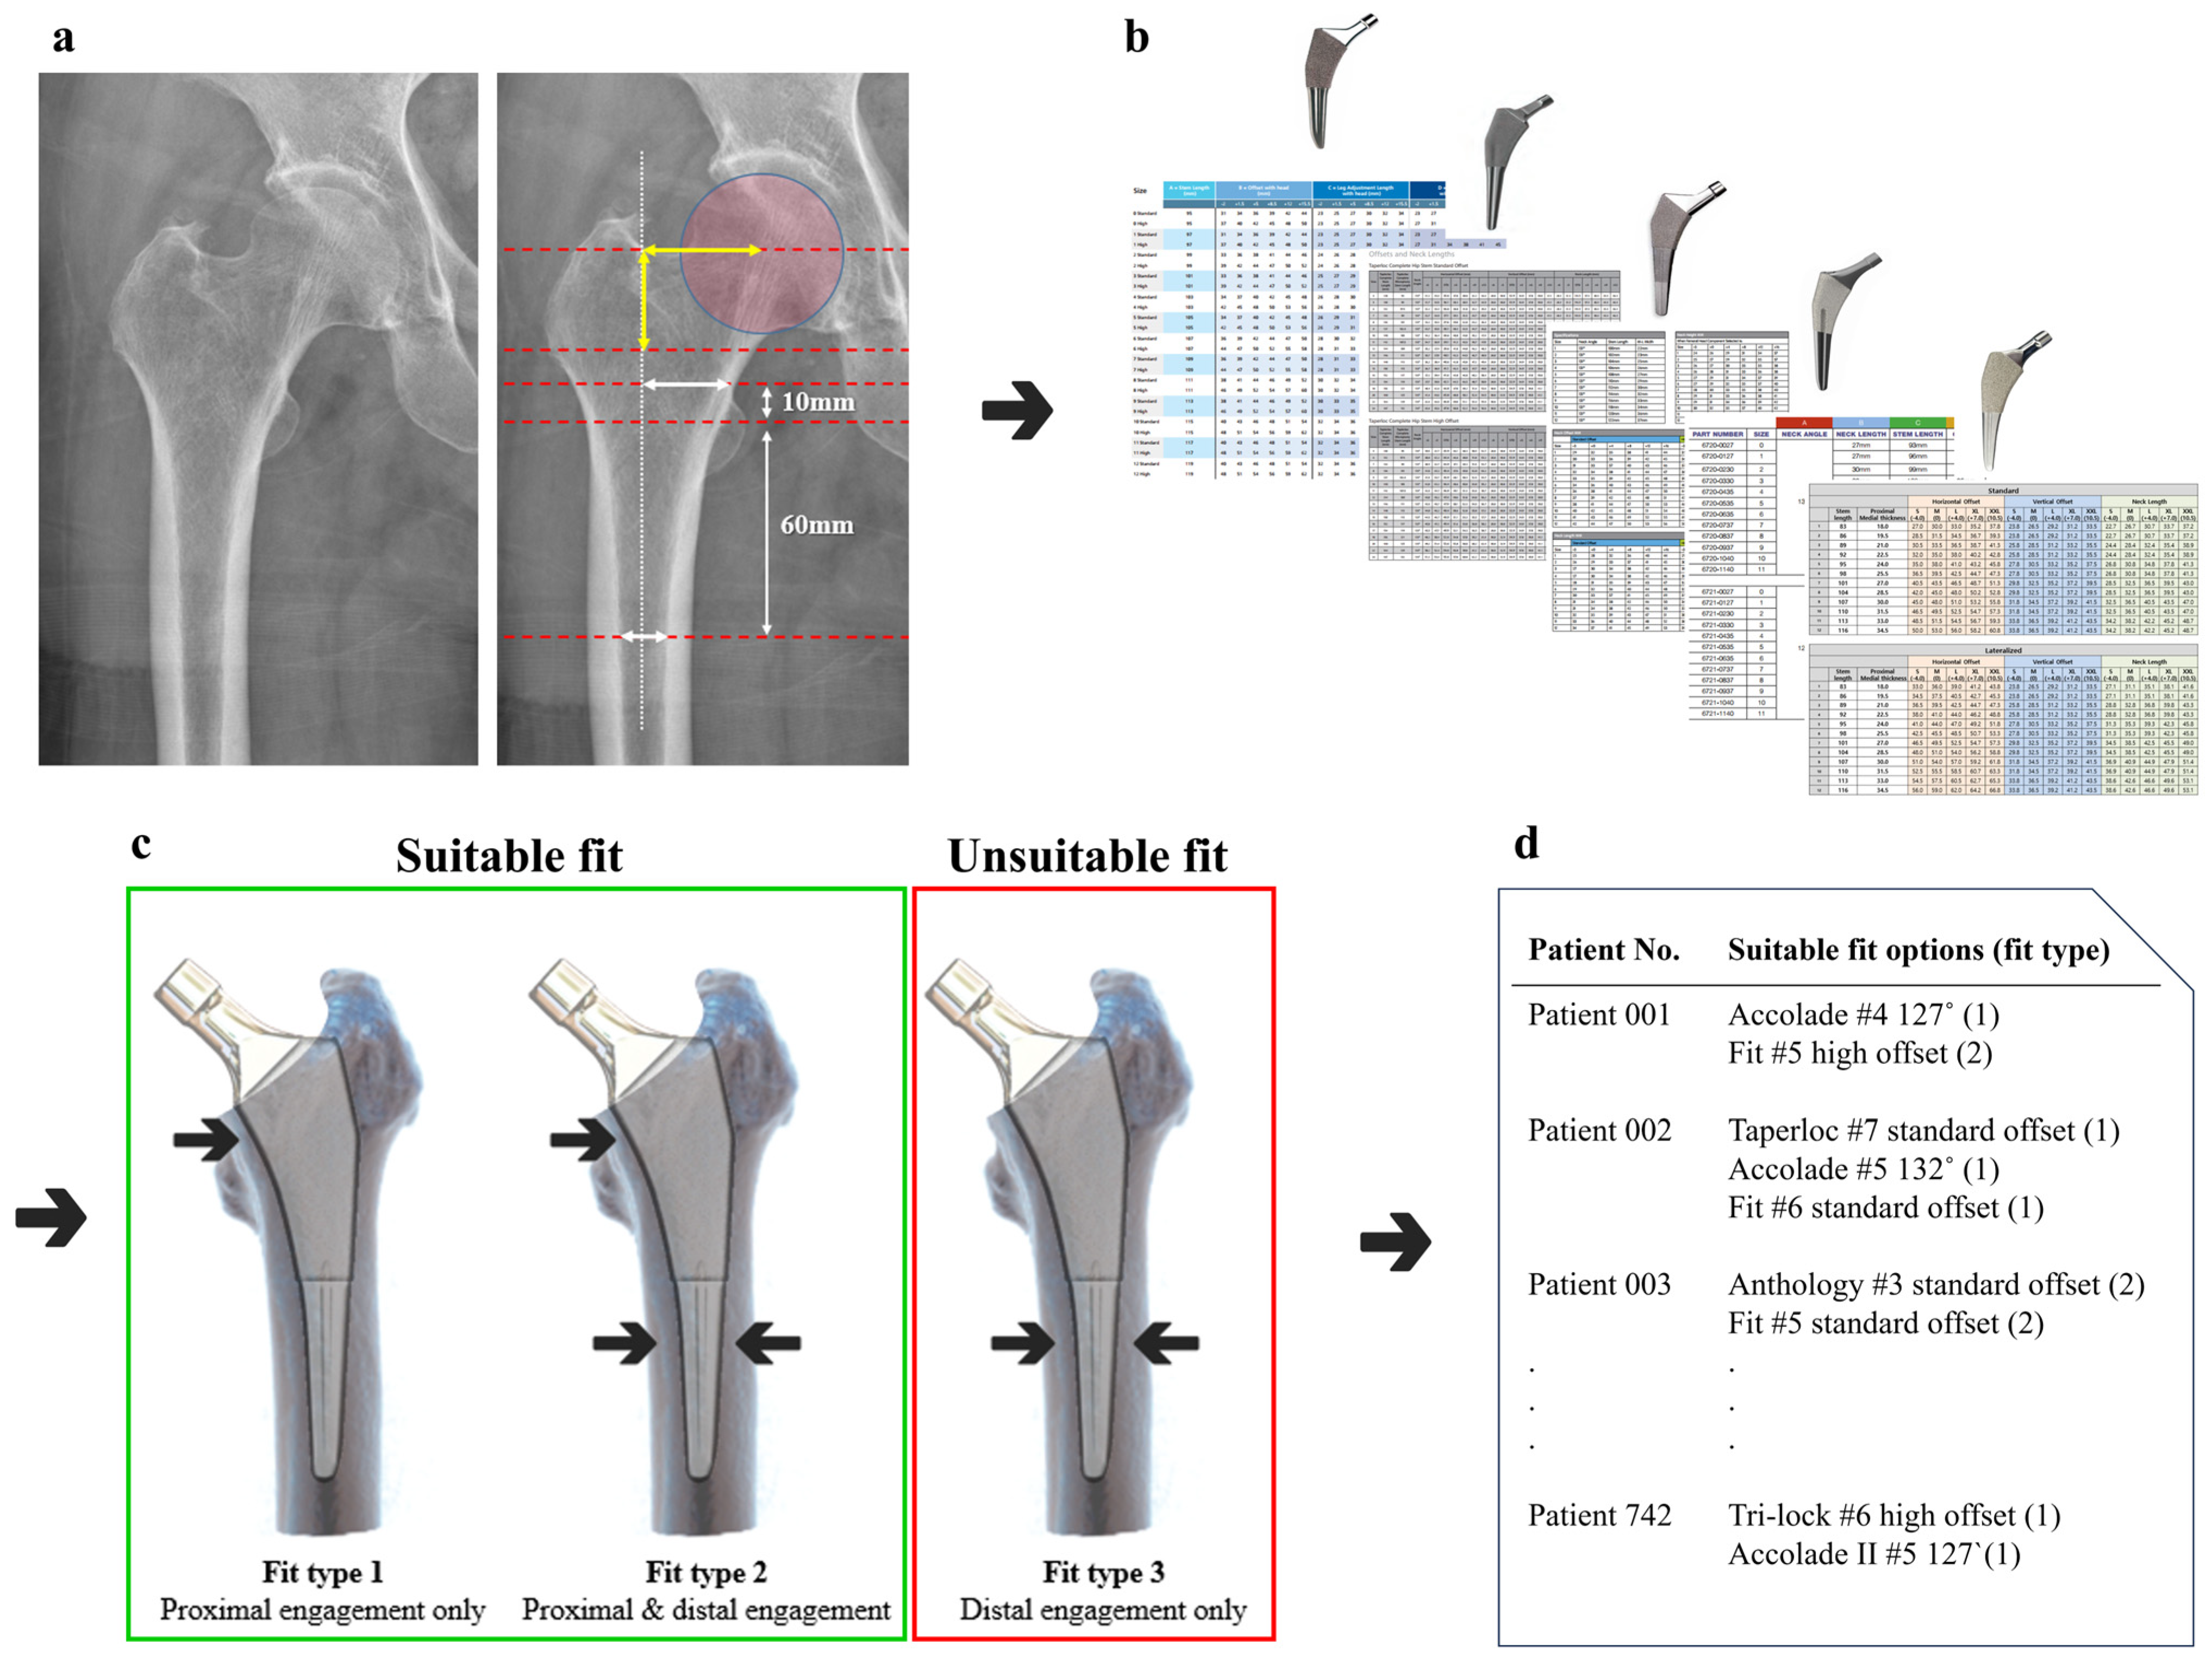

2.6. Offset Analysis

2.7. Fit Analysis Using R Coding

3.3. Fit Analysis